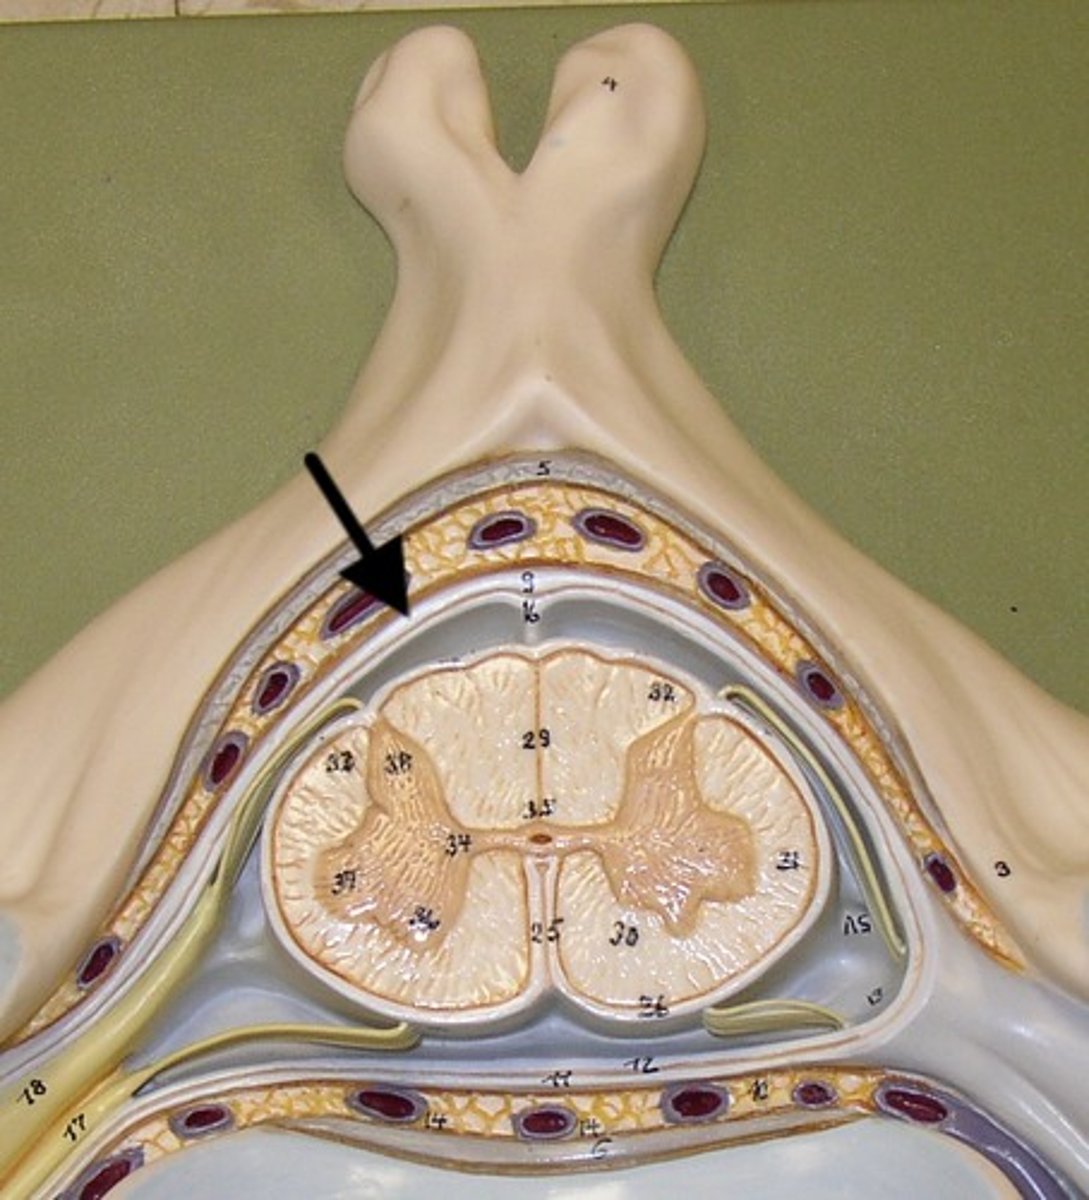

arachnoid mater

middle layer of the meninges

B on model

subarachnoid space

a space in the meninges beneath the arachnoid membrane and above the pia mater that contains the cerebrospinal fluid

pia mater

the delicate innermost membrane enveloping the brain and spinal cord.